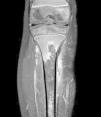

Presentamos el caso de una niña de 6 años con cojera y dolor tibial progresivo de 10 días de evolución, sin fiebre o antecedente traumático. Tanto la paciente como su madre habían sido diagnosticadas previamente de hemoglobinopatía C heterocigota; y su padre estaba diagnosticado de rasgo drepanocítico. La paciente refería haber presentado varios episodios de dolor óseo en distintas localizaciones de miembros superiores e inferiores durante el último año. La exploración física reveló dolor a punta de dedo en la metáfisis proximal de la tibia derecha, sin otros hallazgos significativos. La analítica mostró niveles aumentados de proteína C-reactiva (7,9mg/dl), lactato-deshidrogenasa (420mg/dl) y bilirrubina (1,4mg/dl), sin alteraciones en el hemograma, la coagulación o el resto de parámetros de la bioquímica. Los hallazgos de la radiografía simple fueron normales, por lo que se realizó gammagrafía ósea ante la sospecha de osteomielitis crónica no bacteriana en base a los antecedentes de dolor musculoesquelético de repetición. Ante la captación patológica del trazador exclusivamente a nivel de metáfisis tibial, se indicó una resonancia magnética, que evidenció un infarto óseo agudo de gran tamaño (figs. 1-2). Este hallazgo condujo a la repetición de la electroforesis de hemoglobinas, que detectó un 46% de hemoglobina S y un 44,5% de hemoglobina C, confirmándose así el diagnóstico de hemoglobinopatía SC.